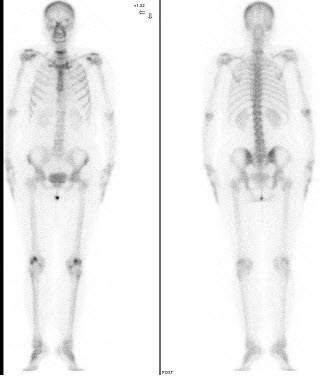

5、多项选择题

男,肝癌术后半年,诉胸背痛3个月,行Tc-MDP骨显像如图,可能的诊断是()

A.大致正常影像

B.胸12骨转移瘤

C.右侧第9后肋“冷区”

D.右侧第9后肋转移瘤

E.右侧第9后肋“甜面圈”征象